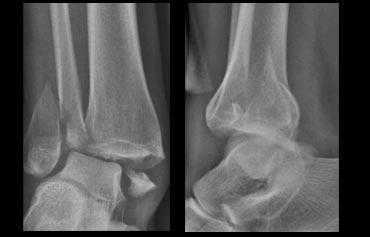

Các hình ảnh cho thấy gãy xương Weber B.

Đường gãy chéo là đặc trưng điển hình của Weber B và là kết quả của sự xoay ngoài của xương sên đẩy vào mắt cá ngoài cố định.

Gãy xương mắt cá thường bắt đầu ở phía trong tại mức vòm xương sên, nhưng cũng có thể bắt đầu cao hơn mức này vài centimet.

Hình ảnh X-quang cho thấy một gãy xương Weber B điển hình.

Hãy quan sát kỹ hình ảnh trước rồi tiếp tục đọc.

Bạn có nhận ra đây là giai đoạn nào không?

Đây là tổn thương Weber B giai đoạn 4.

Lưu ý rằng cả 4 giai đoạn đều có thể nhìn thấy:

- Đứt dây chằng chày mác trước – biểu hiện bằng sự giãn rộng khoảng cách giữa đầu xa xương chày và xương mác (khoảng sáng bên ngoài).

- Gãy xương mác chéo ở mức khớp chày mác – tức là gãy kiểu Weber B.

- Gãy xương Tertius – thấy trên phim thẳng (mũi tên đỏ) và trên phim nghiêng (mũi tên vàng).

- Rupture của dây chằng bên trong – được thấy như sự mở rộng của khoảng cách giữa mắt cá chân trong và xương sên (khoảng sáng trong)

Những hình ảnh này cho thấy một gãy xương Weber B điển hình giai đoạn 4.

Có một đường gãy chéo của xương mác.

Có một gãy giật bong mắt cá sau và một gãy giật bong mắt cá trong.